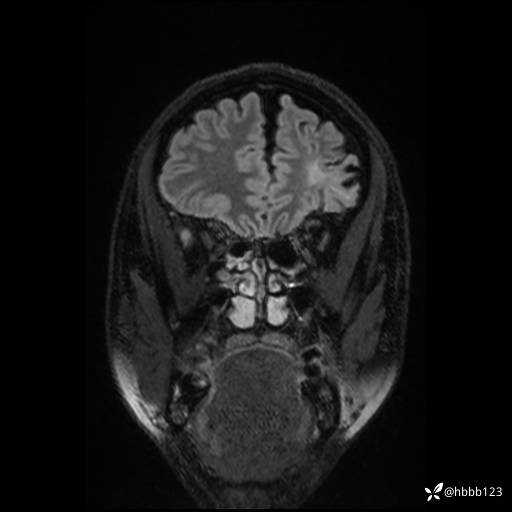

CUBE FLAIR冠状位: